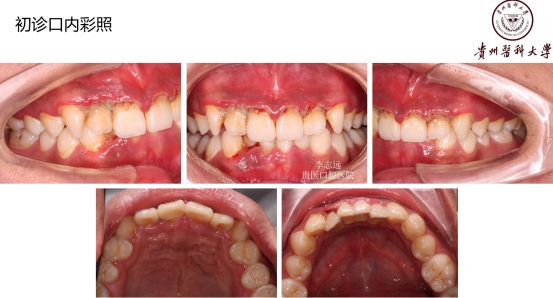

ANUG是指发生于龈缘和龈乳头的急性坏死性炎症。又称战壕口或者梭杆菌螺旋体性龈炎。对牙龈的破坏性很大并且发展很快,在牙龈炎中相当严重!

好发人群以及典型症状:该病好发于青壮年,多见于男性吸烟者、经常熬夜者、精神压力大者。得了这个病的话,前面描述的症状都可能会发生!牙龈的边缘及牙龈乳头发生坏死,常有黄白色假膜覆盖,很痛,有腐败臭味!!但是有这些症状时还是要小心另外一些很严重的疾病哦,比如白血病、艾滋等,得排除了它们,才能放心点。